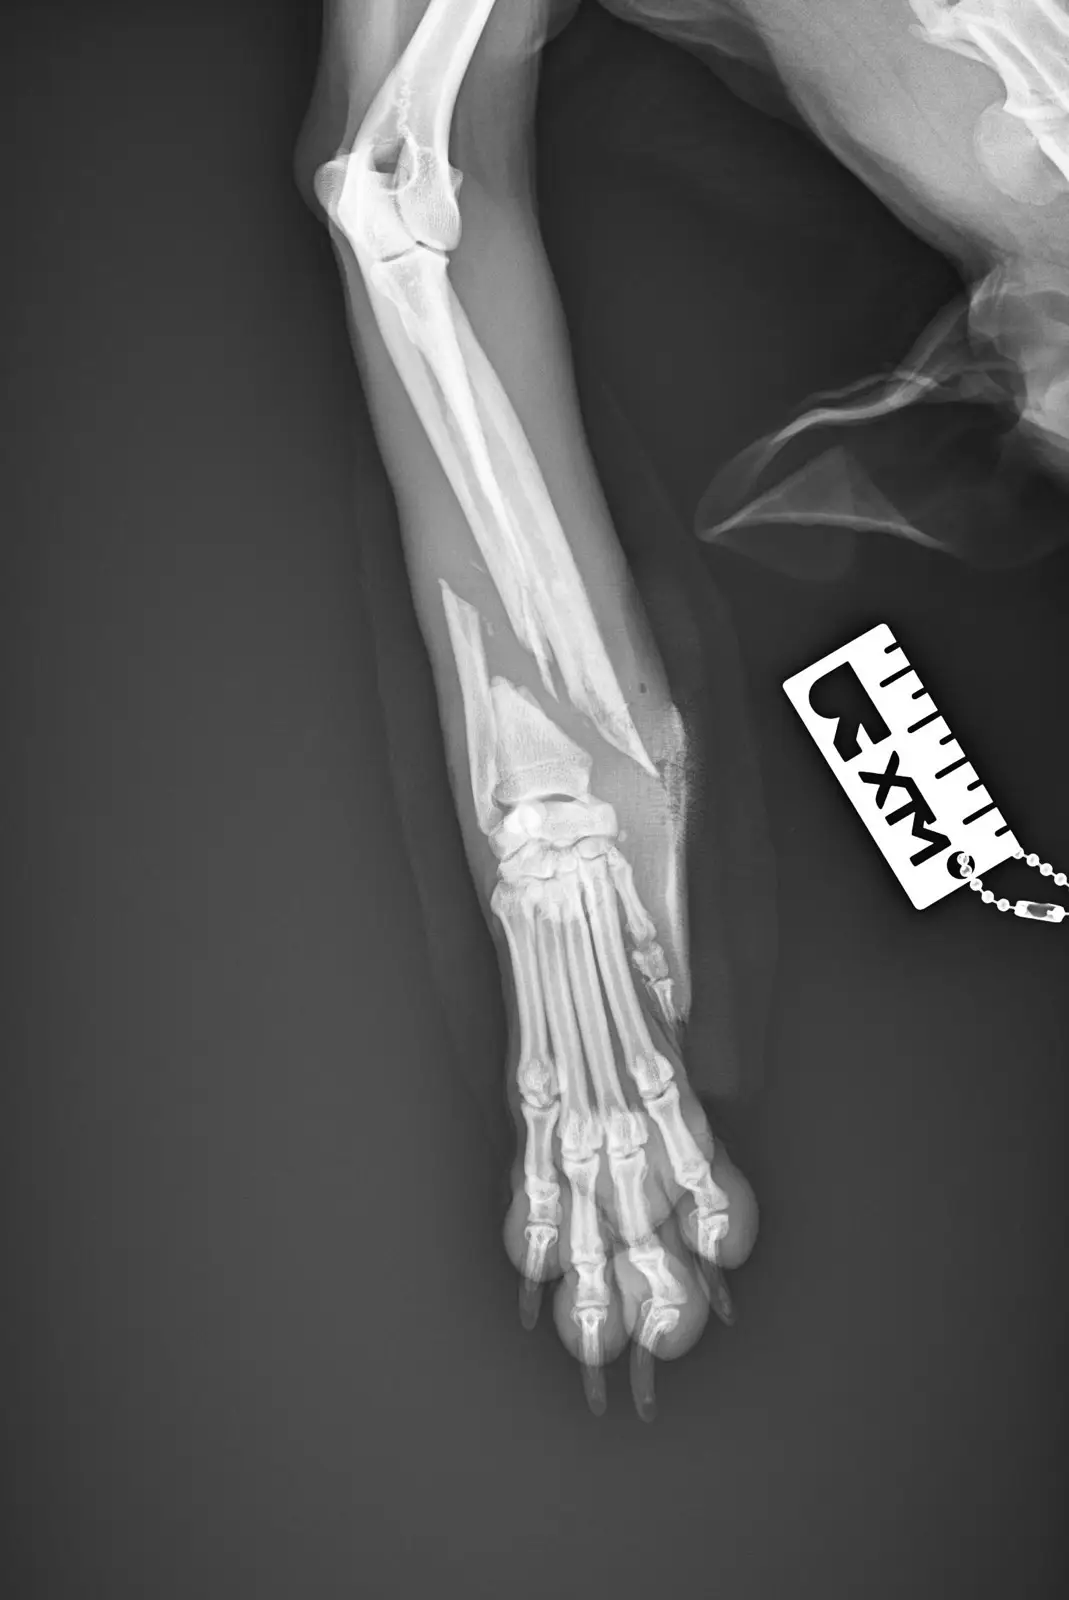

На 14.10.2025г Куче намерено блъснато от кола .

On 14.10.2025 Dog found hit by a car .